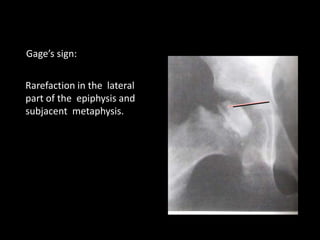

4. gage sign

Rarefaction in the lateral

part of the epiphysis and

subjacent metaphysis.

Gage’s sign:

Catterall - headat risk factors to predict prognosis: 1. Lateral subluxation of femoral head 2. calcification lat. To epiphysis 3. horizontal physeal line 4. gage sign 5. extensive metaphyseal involvement

Rarefaction in thelateral part of the epiphysis and subjacent metaphysis. Gage’s sign: